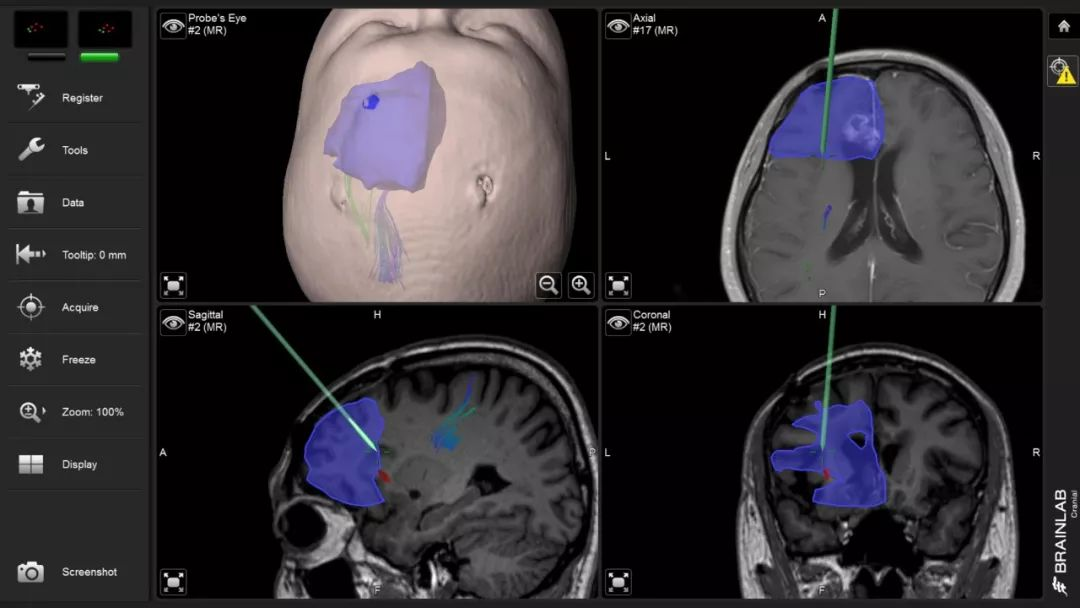

神外资讯将定期分享第一届“凝神聚胶”全国青年医师胶质瘤临床病例分析大赛的获奖病例。本期分享的病例是“二等奖”获得者——福建医科大学附属第一医院吴赞艺医师带来的:“Recurrent Anaplastic Oligodendroglioma Case Sharing(复发间变性少突胶质细胞瘤病例分享)”,欢迎观看、分享。